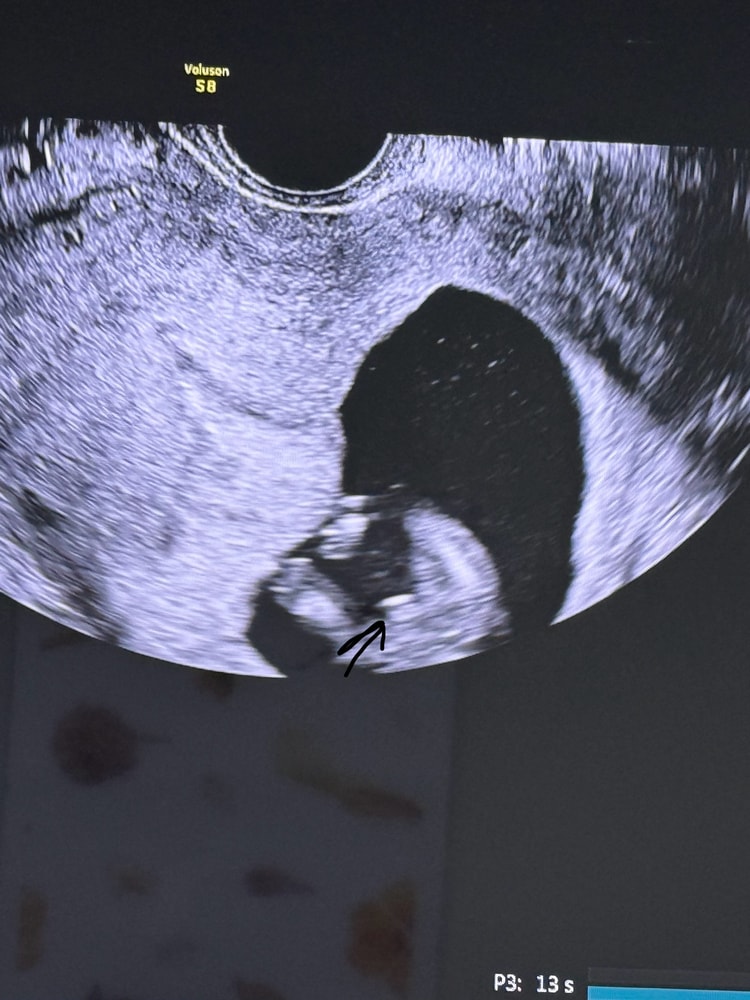

У девочек так не выпячивает) мальчик)

Алия Нурсейтова, нет, там мошонка

Посмотрите в интернете снимки узи девочек